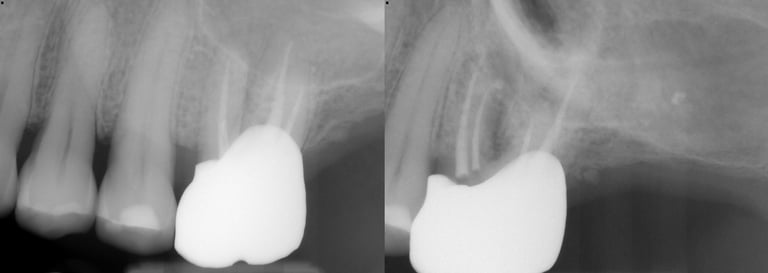

Gallery 2: Retreatment Cases

Retreatment Root Canal Cases with preoperative and postoperative radiographs.

#10 ReTx (original RCT poorly done)

#30 ReTx (original RCT had missed canal)

#14 ReTx (original RCT had missed 4th canal)